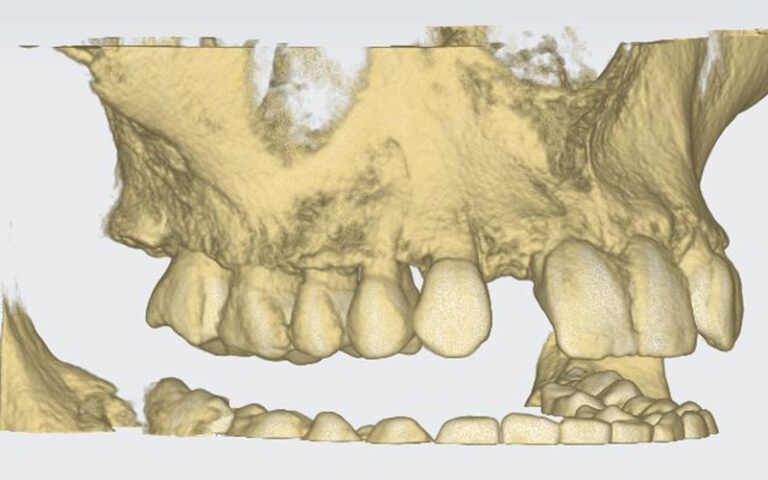

Patient’s initial CT scan after orthodontic treatment Patient’s initial CT scan after orthodontic treatment Patient’s initial CT scan after orthodontic treatment

STL images for planning STL images for planning STL images for planning

After this time a CBCT was taken of the maxilla to start planning the surgery for the placement of two implants in positions 12 and 22. During the analysis of the x-ray images, as the measurements indicate, it was observed that the mesio-distal space between 11-13 and 21-23 was limited, which would impede the placement of two standard implants with a diameter of 3.3 mm.